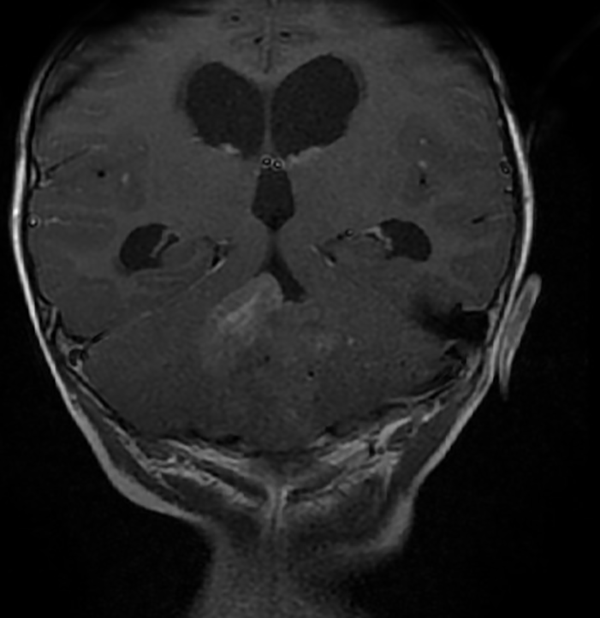

En resonancia magnética (RM) de cerebro se observa tumoración heterogénea sólida o sólido-quística con áreas de hemorragia, quistes y calcificaciones, que capta contraste en forma variable. (Fig. 1, 2, 3, 4). El patrón en espectroscopía se caracteriza por presentar pico de Colina (Cho) y descenso de N-Acetilaspartato (NAA).

Fig 3:

RM corte coronal, secuencia T1 con contraste. Se observa neoformación medial, solido-quística, heterogénea de bordes irregulares en la topografía del VI ventrículo que ocupa la totalidad del mismo, que realza en forma heterogénea tras la administración del contraste. Se observa dilatación triventricular